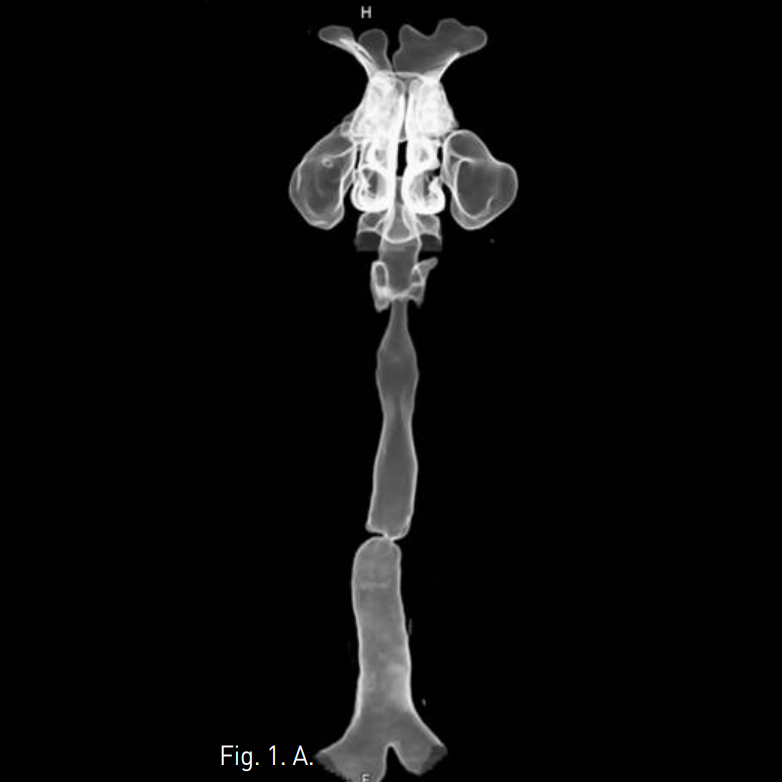

Supine position에서 국소마취 후 bronchoscopic guidance하에 0.035 inch stiff guide wire를 segmental bronchus level 이하까지 전진 시킨 후 5F sizing catheter를 삽입 후 병변의 위치 및 정도를 bronchography를 통하여 확인함. 병변을 확인한 후 15mm 및 20mm x 60mm balloon catheter를 통하여 dilatation을 시행함(Fig. 3). 시술 직후 bronchoscopy에서 web이 찢어지고 내경이 상당히 넓어져 있음(Fig. 4). 한달 후의 투시영상에서 잘 넓어져 있는 상태가 유지됨(Fig. 5).

Fig. 5

On fluoroscopic image 1 month later, resolution of tracheal stenosis was main tained.